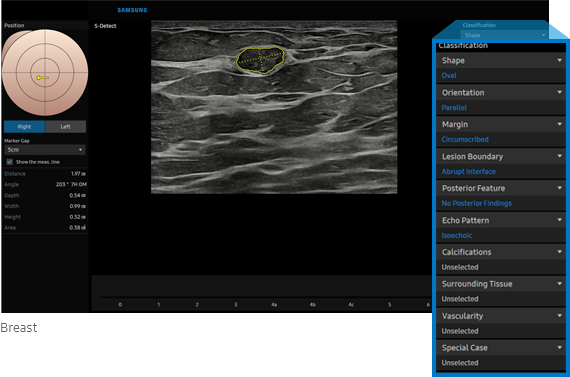

S-Detect™ ¹, ²  for Breast

Semi-automated imaging reporting tool for breast assessment

The feature, which analyzes selected lesions in the breast ultrasound study and shows the analysis data, applies BI-RADS ATLAS* (Breast Imaging-Reporting and Data System, Atlas) to provide standardized reporting; and helps diagnosis with the streamlined workflow.

• Registered trademark of ACR and all rights reserved by ACR.

S-Detec for Breast